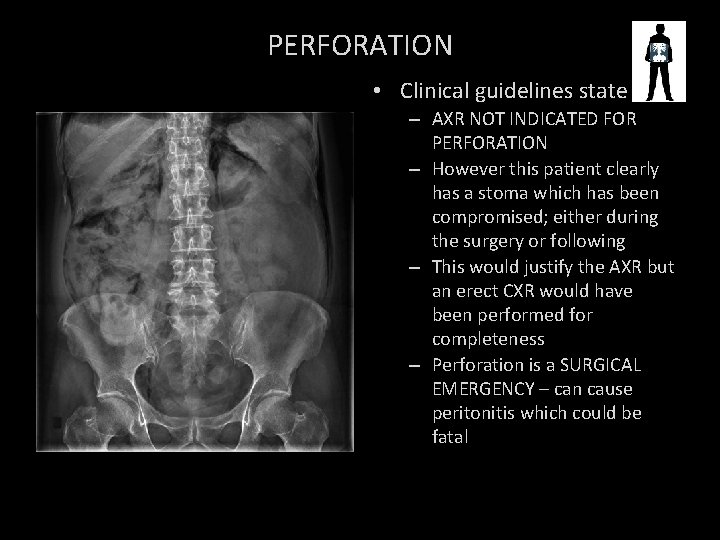

Air in peritoneum stoma PNEUMOPERITONEUM/ACUTE PERFORATION

PERFORATION • Clinical guidelines state – AXR NOT INDICATED FOR PERFORATION – However this patient clearly has a stoma which has been compromised; either during the surgery or following – This would justify the AXR but an erect CXR would have been performed for completeness – Perforation is a SURGICAL EMERGENCY – can cause peritonitis which could be fatal